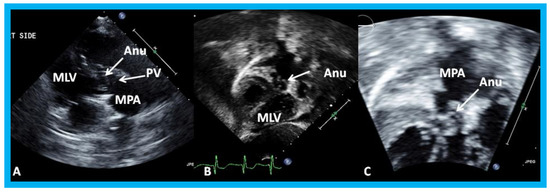

14. Unusual Complication of Supravalvular Pulmonary Artery Stenosis after a Nuss Procedure

An eleven-year-old female patient had a Nuss procedure for treatment of pectus excavatum [30]. A cardiac murmur was heard shortly before the planned Nuss bar removal at the age of thirteen years. Echocardiographic evaluation revealed external compression (Figure 21), causing supravalvar pulmonary stenosis [31]. Removal of the Nuss bar was performed which documented improvement on echo-Doppler studies (Figure 22). Usefulness of echo studies in evaluation of such issues was emphasized.

Figure 19. Selected video frames from a right parasternal (A) and subcostal four chamber (B) views of the morphologic left ventricle (MLV) demonstrating aneurysm (Anu) projecting into the MLV outflow tract, producing obstruction: The Anu is located just below the pulmonary valve (PV). The main pulmonary artery (MPA) is dilated. (C) An enlarged view of B illustrating the aneurysm and MPA dilatation. Reproduced from Yarrabolu T.R., et al. [23].